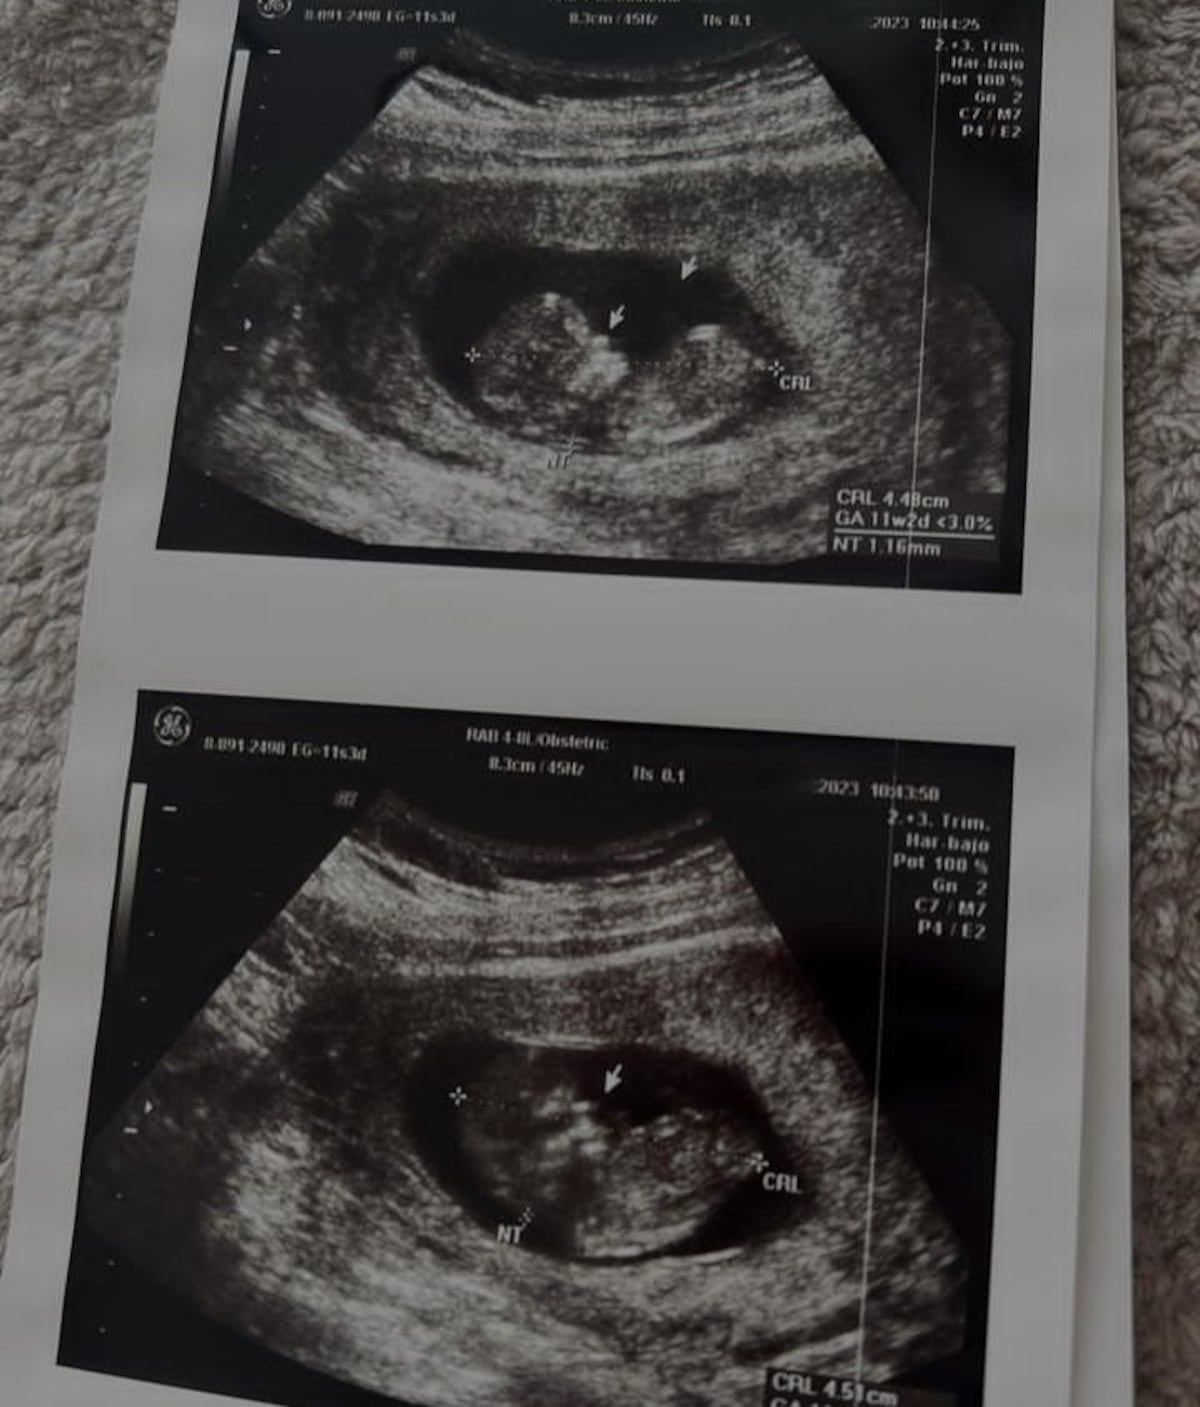

Además de mostrar los ultrasonidos del bebé, enseñó un lindo par de medias que ya le compró.